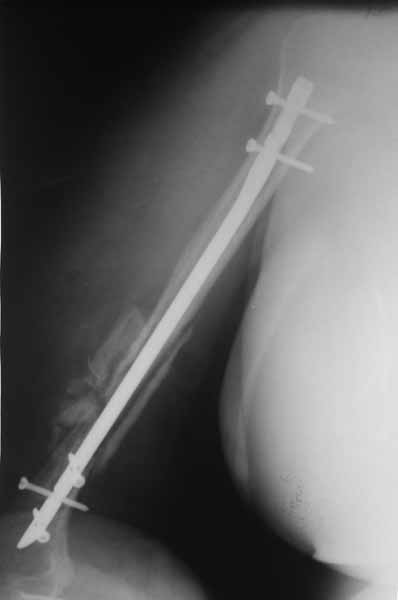

Плечевой сустав на сегодняший день спустя 10 мес. после травмы.

[ Ответить ]